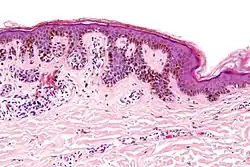

| Type | Characteristics | Photo- graphy |

Histo- pathology |

|---|---|---|---|

| Dysplastic nevus | Usually a compound nevus with cellular and architectural dysplasia. Like typical moles, dysplastic nevi can be flat or raised. While they vary in size, dysplastic nevi are typically larger than normal moles and tend to have irregular borders and irregular coloration. Hence, they resemble melanoma, appear worrisome, and are often removed to clarify the diagnosis. Dysplastic nevi are markers of risk when they are numerous, such as in people with dysplastic nevus syndrome. According to the National Institute of Health (NIH), doctors believe that, when part of a series or syndrome of multiple moles, dysplastic nevi are more likely than ordinary moles to develop into the most virulent type of skin cancer called melanoma.[19] | ![]() In this case, the central portion is a complex papule, and the periphery is macular, irregular, indistinct and slightly pink. |

Characteristic rete ridge bridging, shouldering, and lamellar fibrosis. H&E stain.

|